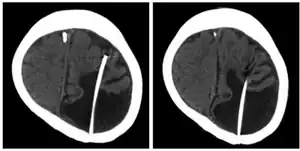

The presence of porencephalic cysts or cavities can be detected using trans-illumination of the skull of infant patients. Porencephaly is usually diagnosed clinically using the patients and families history, clinical observations, or based on the presence of certain characteristic neurological and physiological features of porencephaly. Advanced medical imaging with computed tomography (CT), magnetic resonance imaging (MRI), or with ultrasonography can be used as a method to exclude other possible neurological disorders. The diagnosis can be made antenatally with ultrasound. Other assessments include memory, speech, or intellect testing to help further determine the exact diagnose of the disorder.[3]

There is no cure for porencephaly because of the limited resources and knowledge about the neurological disorder. However, several treatment options are available. Treatment may include physical therapy, rehabilitation, medication for seizures or epilepsy, shunt (medical), or neurosurgery (removal of the cyst).[3] According to the location, extent of the lesion, size of cavities, and severity of the disorder, combinations of treatment methods are imposed. In porencephaly patients, patients achieved good seizure control with appropriate drug therapy including valproate, carbamazepine, and clobazam.[7][8] Also, anti-epileptic drugs served as another positive method of treatment.[8]